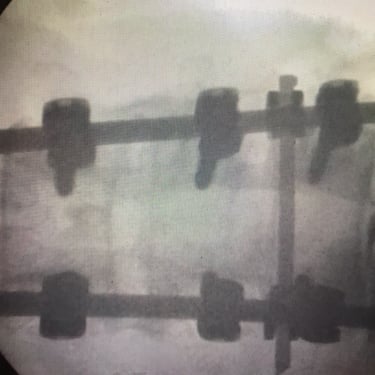

An intriguing case involved severe herniation and disc rupture between L4 and L5 vertebrae, causing intense pain. Opting out of surgery, the patient chose to try Discogel. Due to severe foraminal stenosis from the extruded disc, the Discogel injection was cautiously prolonged to one hour. Post-injection CT scan revealed effective penetration into fragmented disc components in the narrowed foraminal space.

The patient's pain gradually diminished after 4-5 weeks, and complete relief was achieved after several months.

The first image is six months post-injection, and the second image is three years post-injection."